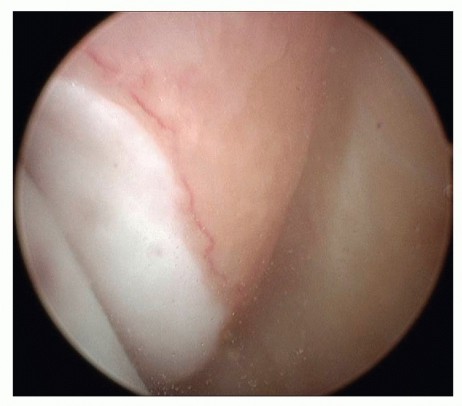

Ligament lesions are graded as distended if the ligament is thinned or elongated and as ruptured if

continuity is lost.8 Most ligament tears are located on the proximal insertion; this is best seen by a completely free insertion area of the ligament on the malleoli (TECH FIG 1).

- TECH FIG 1 • Avulsion of the anterior superficial layers from the medial malleolus. Arthroscopy typically reveals a completely free insertion area of the ligament on the medial malleolus.